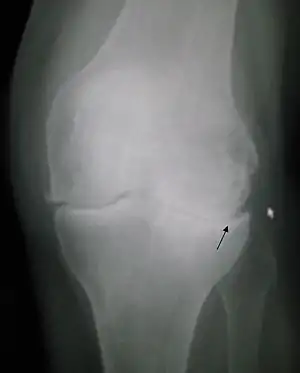

| کاهش فاصله مفصل و ایجاد استخوانرُست در آرتروز زانو | |

حفظ وزن در حد مناسب، داشتن فعالیت فیزیکی مناسب، تغذیه مناسب باعث پیشگیری بیماری میشود. تشخیص اصولاً بالینی است. بررسیهای تشخیصی ممکن است شامل بررسی آزمایشگاهی مایع مفصل (برای ردکردن احتمال آرتریت التهابی) باشد. رادیوگرافی و مفاصل درگیر، میزان کاهش فاصله مفصلی، اسکلروز و گاه کیست زیر غضروفی را نشان میدهد.

علائمی که در اشعه ایکس دیده می شود عبارتند از:

- تنگ شدن فضای بین مفصلی

- افزایش حجم استخوان در اطراف مفصل

- تشکیل کیست [1]

پس از تشخیص اولیه (بالینی) اشعه ایکس می تواند بیماری را تایید کند